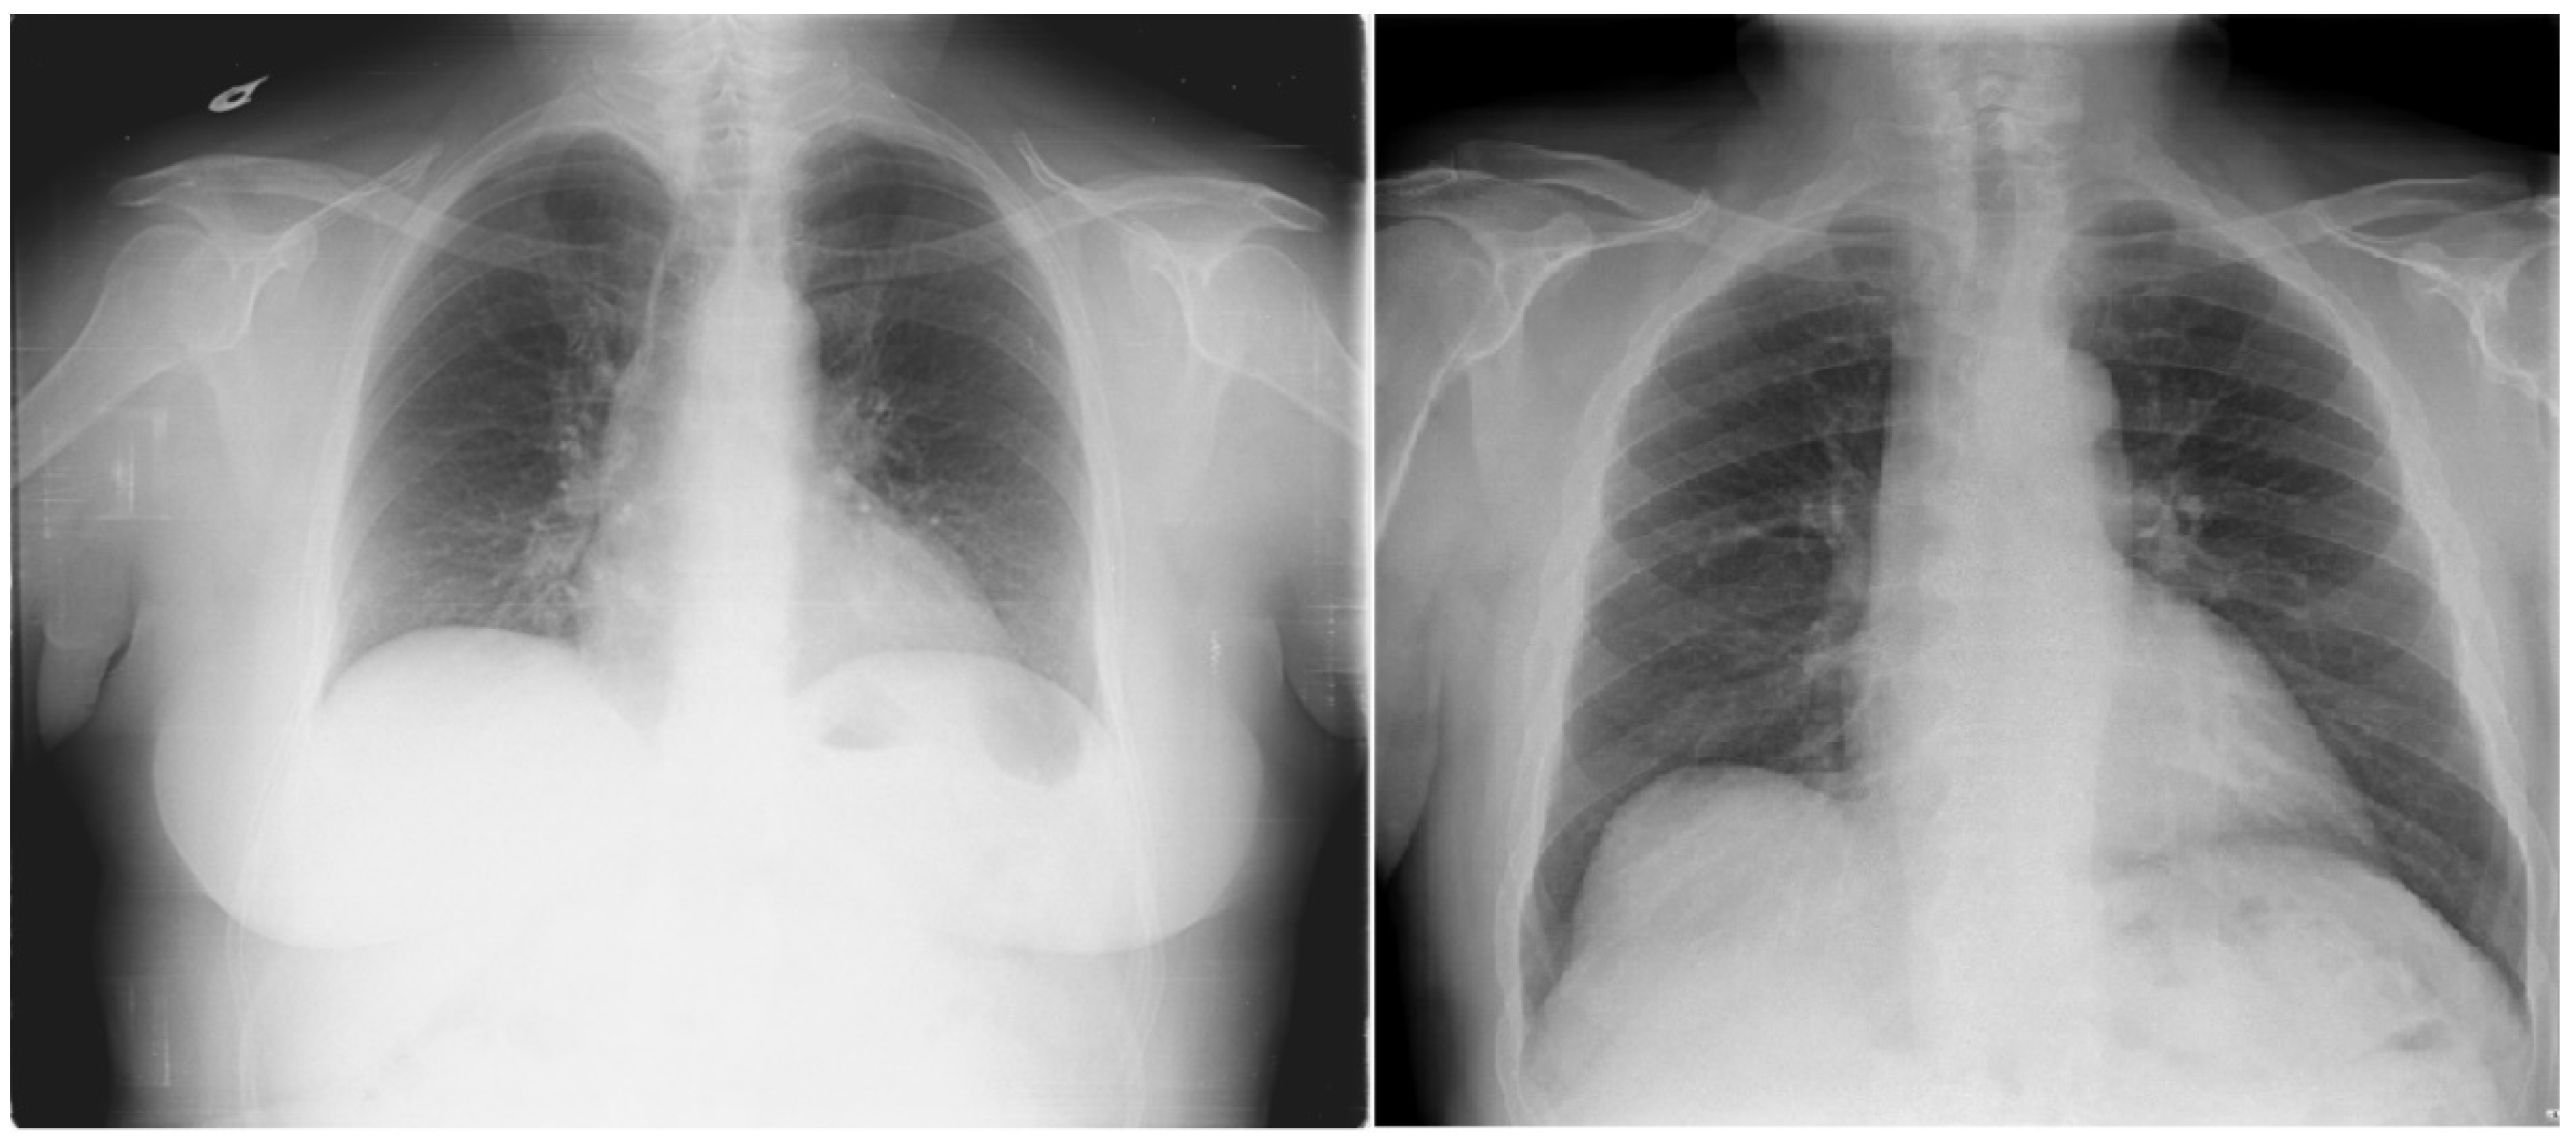

Cardiomegaly, characterized by an enlargement of the heart muscle, is often considered a marker of underlying cardiac conditions and is associated with increased morbidity and mortality. Early diagnosis plays a critical role in improving patient outcomes, particularly given that cardiovascular diseases (CVDs) are among the leading causes of global mortality, accounting for approximately one-third of annual deaths [1]. Early identification and management of cardiomegaly can significantly improve patient outcomes [2]. Imaging techniques hold a central position in the diagnostic process for CVDs, as they facilitate the detection of structural changes in the heart, such as those seen in cardiomegaly. Figure 1, for example, illustrates normal heart anatomy alongside the anatomical changes associated with cardiomegaly [3]. Key clinical indicators of cardiomegaly include dyspnea (shortness of breath), which occurs mainly during exertion or while lying down and is often correlated with elevated biomarkers such as B-type Natriuretic Peptide (BNP) and N-terminal pro B-type Natriuretic Peptide (NT-proBNP), which reflect cardiac strain [4].

Figure 1.

Comparative heart anatomy: (a) illustration of a typical heart; (b) demonstrating the anatomical changes associated with an enlarged heart [3]. The dotted line indicates the direction of expansion of the heart.